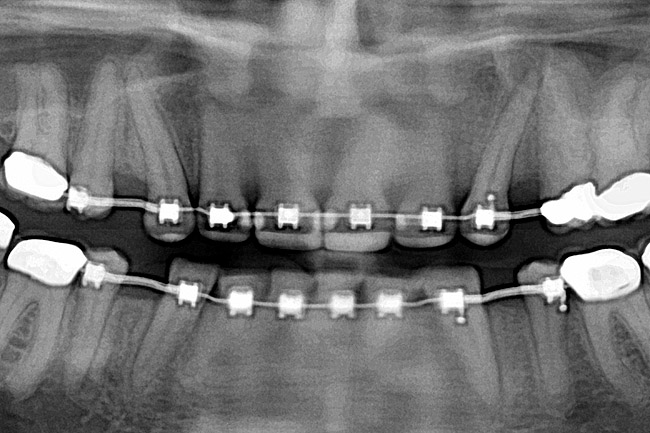

Figure 11

Fig 12 (and Fig 13). Incisors were too upright and had severe incisal wear. He was concerned about esthetics of the worn teeth and his insufficient lip support. Progress photo and panorex 9 months after corticotomies were performed on Nos. 6 through 11. Previous extraction sites were reopened orthodontically to improve function and fill lip support. Incisal edges were restored provisionally with composite resin. Note that despite the creation of adequate spaces to replace missing teeth, there is inadequate room for placement of dental implants because of severe tipping of all the anterior teeth. Osteotomy SFOT may have been a better choice because it would have allowed needed alveoloskeletal correction (without excessive tipping) instead of the primarily dentoalveolar correction common in corticotomy SFOT. Restorative dentist: Brad Jones, DDS.

Fig 13 (and Fig 12). Incisors were too upright and had severe incisal wear. He was concerned about esthetics of the worn teeth and his insufficient lip support. Progress photo and panorex 9 months after corticotomies were performed on Nos. 6 through 11.